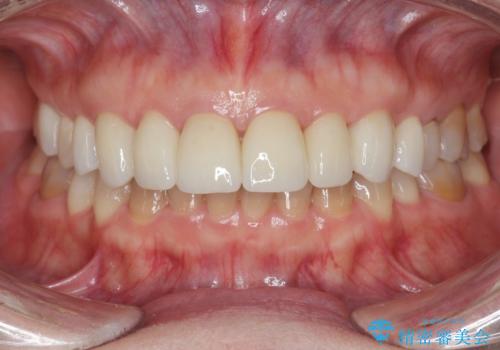

ラミネートよりもより透明感の再現性の高いジルコニアクラウンの出来に喜んでいただくことが出来ました。